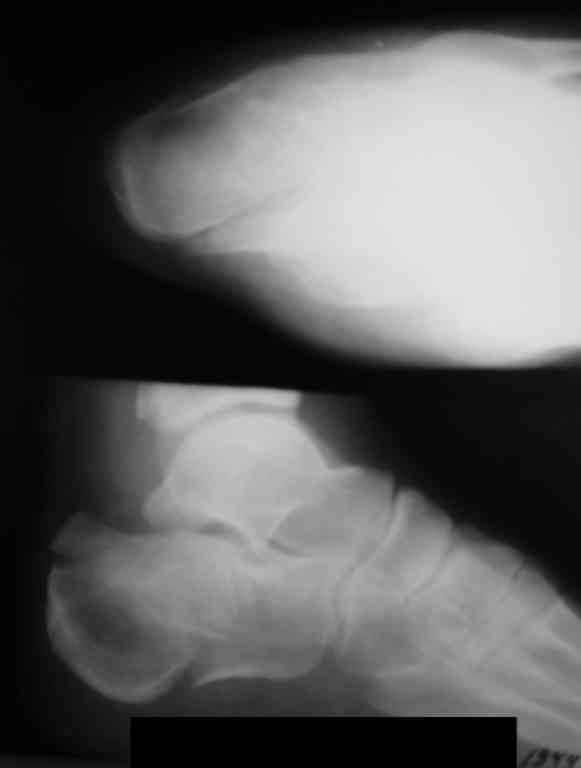

[Ortho] Перелом пяточной кости

Как лучше фиксировать такой перелом пятки?